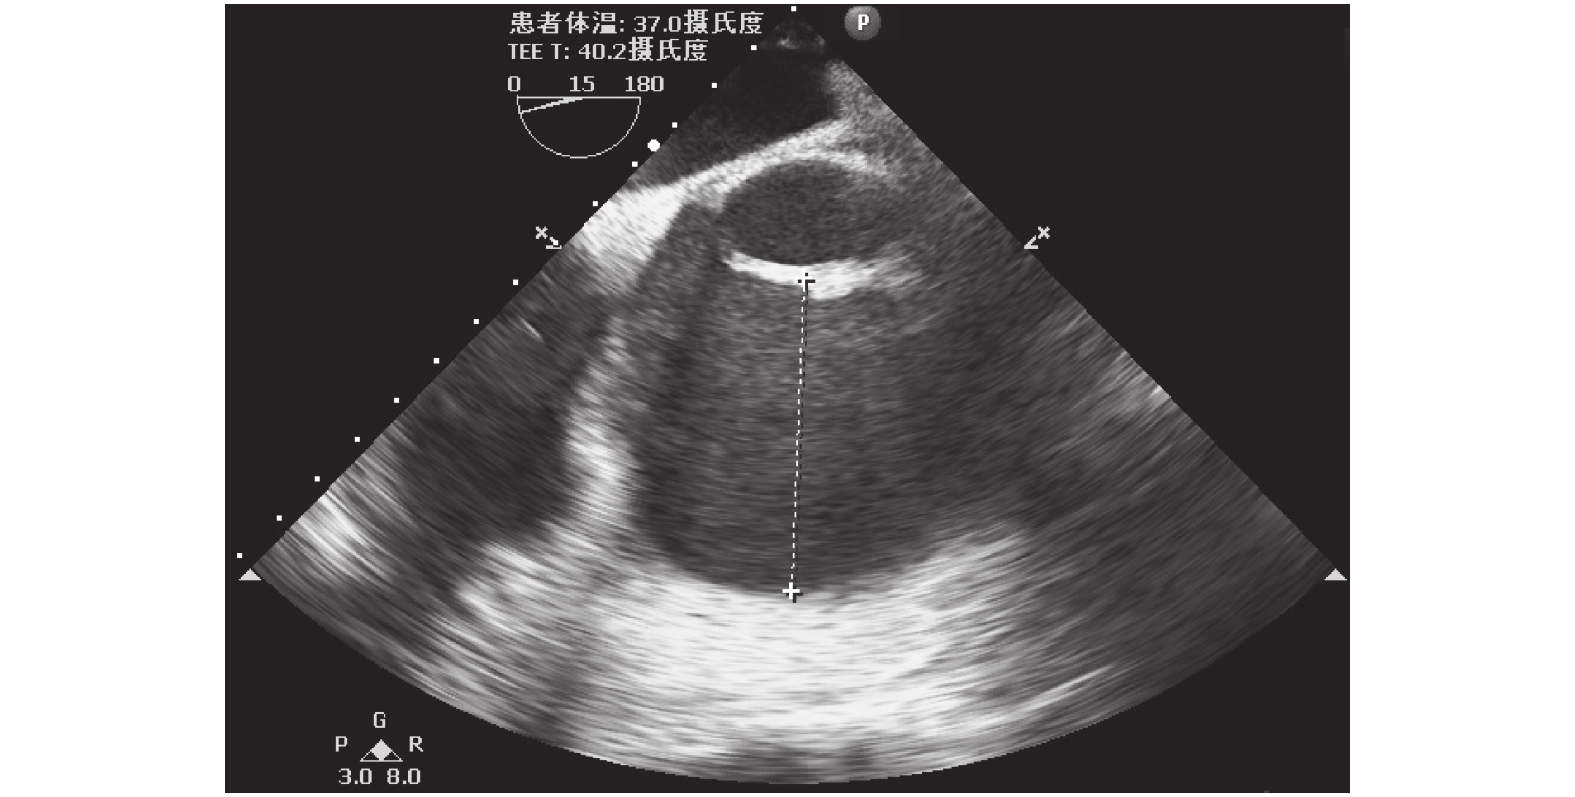

患者入手術室后進行心電監護,局部麻醉下行左側橈動脈穿刺置管連續監測動脈血壓。使用咪達唑侖 8 mg,枸櫞酸舒芬太尼 50 μg,順式阿曲庫銨 15 mg 緩慢靜脈推注誘導后插管,機械通氣潮氣量 8 ml/kg,呼吸頻率 12 次/min。右側頸內靜脈穿刺置管監測中心靜脈壓(CVP),置入經食管超聲心動圖(TEE)探頭。術中常規主動脈、上下腔靜脈插管,體外循環(CPB)轉機、降溫至 33℃,升主動脈遠段阻斷主動脈,經主動脈根部灌入含血心臟停跳液,心包內局部置入冰屑,心臟停跳。CPB 期間丙泊酚聯合瑞芬維持麻醉,平均動脈壓(MAP)45 mm Hg,加用去甲腎上腺素 0.03 μg/(min·h),維持 MAP 50 mm Hg。術中搭橋 2 根,分別為左乳內動脈-左前降支,升主動脈-大隱靜脈-第一對角支,切開右房、房間隔行二、三尖瓣成形術,復溫至體溫 36.5℃,開放升主動脈,心臟自動復跳,靜脈泵注腎上腺素 0.05 μg/(kg·h),去甲腎上腺素 0.08 μg/(kg·h),異丙腎上腺素 0.03 μg/(kg·h),米力農 0.05 mg/(kg·h),間斷推注去甲腎上腺素 20 μg,心率 110 次/min,全身動脈血壓(ABP)維持 84~70/56~46 mm Hg。動脈血氣示:pH 7.4,鉀 3.42 mmol/L,鈣 1.09 mmol/L,血糖 9.7 mmol/L,剩余堿(BE)–5.79 mmol/L。予補鉀、補鈣后,加用垂體后葉素 3 U/h,ABP 仍維持 80/48 mm Hg 左右,CVP 10 mm Hg。TEE 監測提示循環容量充足(左室舒張期末內徑 5.65 cm),心臟收縮功能良好(圖 1 、圖 2)。復查動脈血氣未見內環境紊亂。CPB 停機后患者尿量 180 ml/h,肢端溫暖。外科醫師于主動脈根部穿刺測壓 95/59 mm Hg。麻醉醫師行術中股動脈穿刺置管測壓,同時監測患者橈動脈與股動脈壓力,患者股動脈 MAP 波動于 60~70 mm Hg,較橈動脈 MAP 增高約 20 mm Hg。體外循環轉流時間 196 min,主動脈阻斷 126 min,流量 3.6 L/min。術后患者體溫 36.5℃,心率 95 次/min,股動脈血壓 103/60 mm Hg,SpO2 100.0%,靜脈持續泵注腎上腺素 0.03 μg/(kg·h),去甲腎上腺素 0.05 μg/(kg·h),順利返回心胸外科重癥監護室。術后予呼吸機輔助通氣、強心、利尿,維持內環境等對癥支持治療。患者基礎心功能差,術后第 2 d 持續應用腎上腺素 0.05 μg/(kg·h),去甲腎上腺素 0.05 μg/(kg·h),米力農 0.5 mg/(kg·h),垂體后葉素 2 U/h 維持循環。查體心率 90 次/min,血壓 110/63 mm Hg,SpO2 100.0%,四肢溫暖,雙肺呼吸音清,小便量正常,心包縱隔引流管通暢,引流量不多。患者術后第4 d 小便量明顯減少,肌酐升高,查體心率 103 次/min,股動脈 102/59 mm Hg,SpO2 99%,持續泵注腎上腺素 0.03 μg/(kg·h),米力農 0.2 m/(kg·h) 強心治療。術后第 6 d 查體心率 89 次/ min,血壓 112/65 mm Hg,SpO2 99%,停用所有血管活性藥物,局部麻醉下行纖維支氣管鏡檢查后順利拔除氣管導管。

圖2

停機后左室 TEE 二維圖